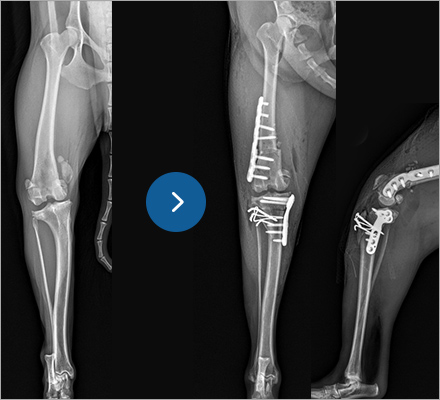

치료 후기

테루는 재작년 다른 병원에서 슬개골 탈구 4기 수술 후, 재탈구가 되어 재수술 불가 판정을 받았었습니다.

그러나 예은동물의료센터에서 상담 후 이전과 달리 정확한 원인을 짚어주시며 재수술이 가능하다

말씀해주셔서 무사히 재수술을 받게 되었습니다. 양쪽 다리 수술이 모두 끝난 지금, 테루의 다리는 정말 튼튼합니다.

어찌나 잘 뛰는지 산책시키는 제 다리까지 건강해질 지경입니다. 테루가 다시 실컷 뛰어놀 수 있게 해주신

예은동물의료센터 선생님들께 진심으로 감사드립니다.

흔하지 않은 케이스라 힘든 수술이 되었지만 반드시 잘 될거라고 말씀해주셔서 얼마나 안심이 됐는지 모릅니다.

혹시나 제 잘못 때문에 테루가 아픈게 아닐까 하는 마음이 있었는데 보호자님 잘못이 아니라 말씀해주시고,

카운터 선생님들도 늘 밝은 분위기로 맞이해주셔서 마음이 얼마나 편해졌는지 몰라요. 테루의 다리 뿐만 아니라,

무거웠던 마음까지 치료해주신 것 같아 지금도 마음 깊이, 다시 한 번 감사드립니다!